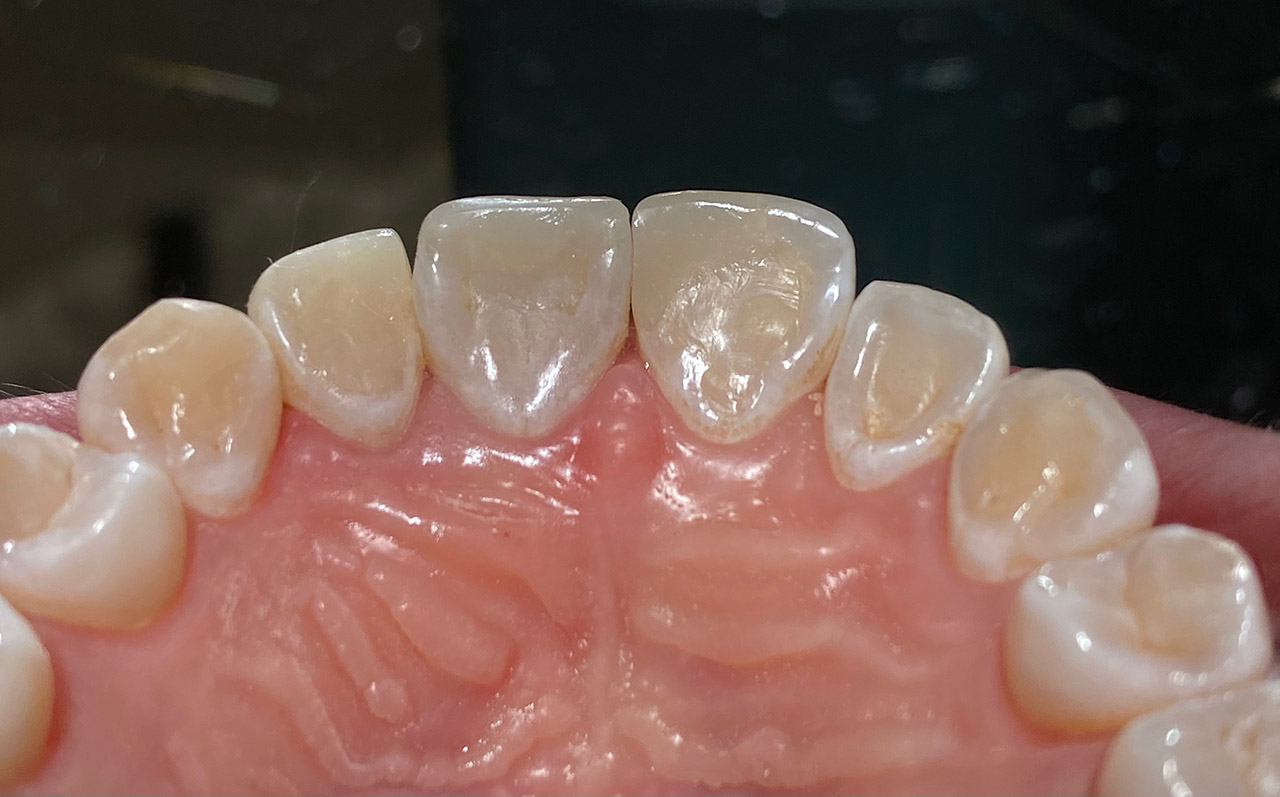

Prophylaxe/professionelle Zahnreinigung:

Zur Motivation, Information und Instruktion einfärben der Beläge (bakterieller Biofilm) bei jungem Patienten in kieferorthopädischer Behandlung. Reinigung der Zähne mit Pulverstrahltechnik minimalinvasiv und zahnschonend und wo noch nötig gezielt mit Ultraschall.

Das Resultat 45 Minuten später.